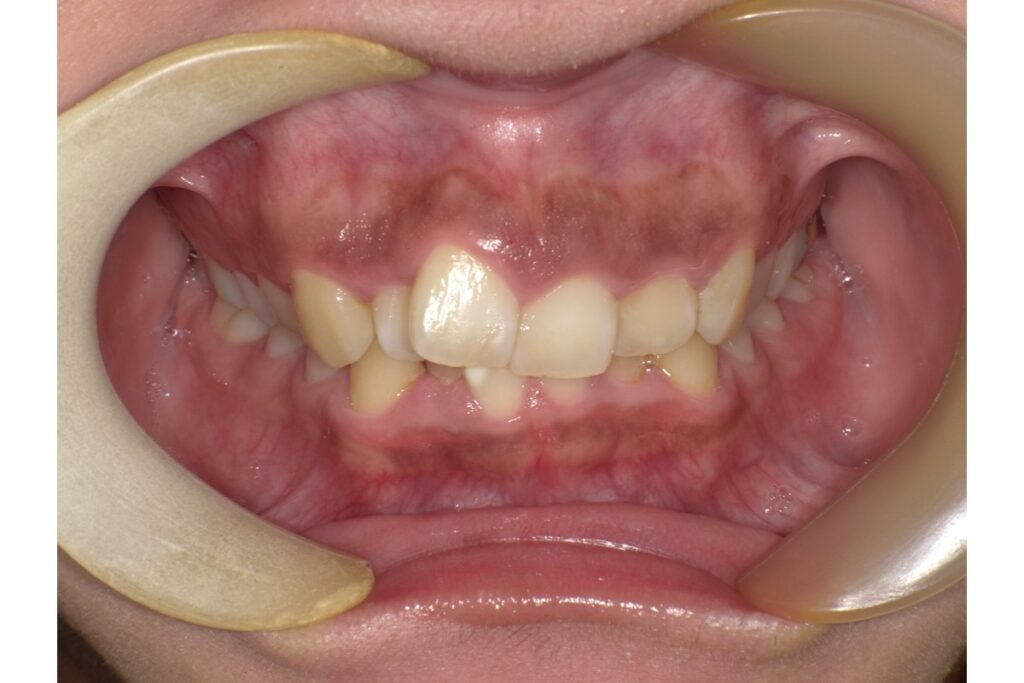

2. 出っ歯(上顎前突)

前歯が前方に突出している出っ歯も、抜歯矯正の対象となることがあります。特に、前歯が唇を押し出している、口が閉じにくい、横顔で口元が突出して見えるなど、見た目や機能的に問題がある場合は、抜歯で前歯を後退させることが有効です。